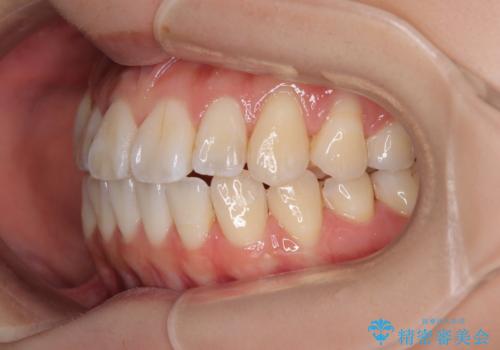

舌の突出癖が原因 インビザライン矯正による開咬改善

- 前歯の開咬を気にして来院された患者様です。

開咬の治療は、前歯を閉じるように動かすとともに、上下臼歯を圧下(骨内にめり込ませる)させることで進めて行きます。

インビザラインは臼歯の圧下を効果的に行えるため、インビザラインを用いて矯正治療を行うこととしました。